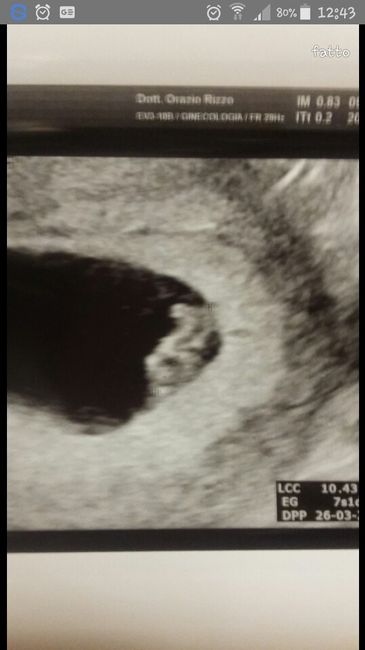

Salve a tutte, qualcuna per gioco che ci capisce (sicuramente mooolto più di me ) con tutti questi metodi ramzi ecc... cosa potrebbe essere? Grazie già in anticipo 😊 ... e spero di avere qualche risposta questa volta 🤞🏼 Questa eco è di 10+ 5...